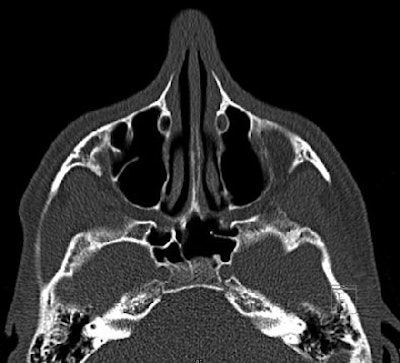

| Normal low-dose CT examination of sinuses of 14-year-old boy (16-slice CT, phase 1; effective dose, 0.11 mSv). 2.5-mm axial image shows normal maxillary and sphenoid sinuses (AJR 2005; 184:1611-1618). |